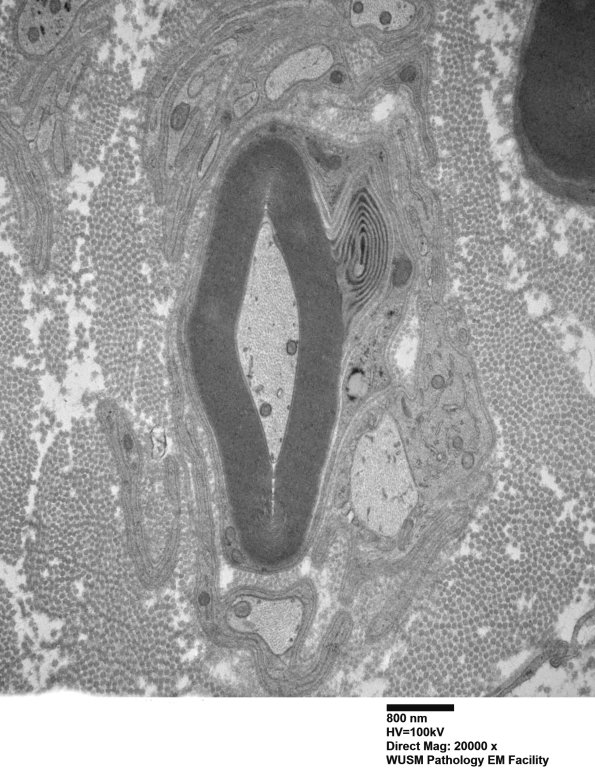

Washington University Experience | PERIPHERAL NEUROPATHY | 12 ANTI-MAG NEUROPATHY | 9C1A (Case 9) Nerve_007 - Copy

9C1A,B Here the Schmidt-Lanterman cleft is in correspondence to myelin change which is not compelling for WSM. (electron micrograph)